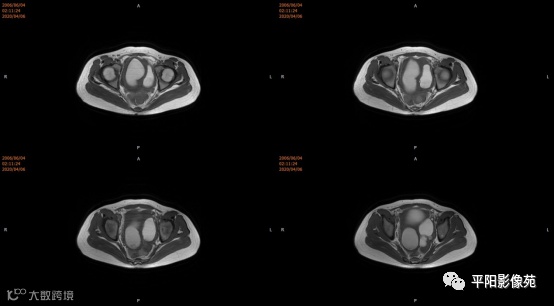

患者,女,13岁

主诉: 下腹部胀痛2+月,加重1天

现病史: 患者月经未来潮,2+月前无明显诱因感下腹部憋胀,间断胀痛,可忍耐,伴排便困难,自认为便秘引起腹胀,未在意。近1+月腹胀、胀痛次数增加,觉下腹部逐渐增大,小便正常。

您的诊断?

4.MRI检查 对软组织分辨率好,能够清晰区分子宫及阴道,对子宫内膜、结合带、肌层可清晰分辨;能明确子宫、宫颈、阴道结构异常的部位、范围、性质等。宫腔内经血潴留时,宫腔内见短T1长T2信号。